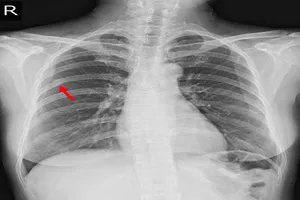

13. 폐렴

폐렴은 폐에 염증이 생겨 숨쉬기가 힘든 질환입니다. 감기에 걸렸을 때처럼 기침이 나고 가래가 끓으며, 열이 나고 가슴이 아픈 증상이 나타날 수 있습니다. 항생제를 사용하여 치료하고 충분히 쉬는 것이 중요합니다.

폐렴